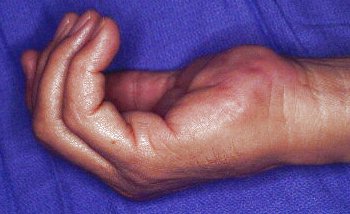

This rubbery hard mass developed over the course of a year. There was a history of some repeated impact to the area.

Click for larger image